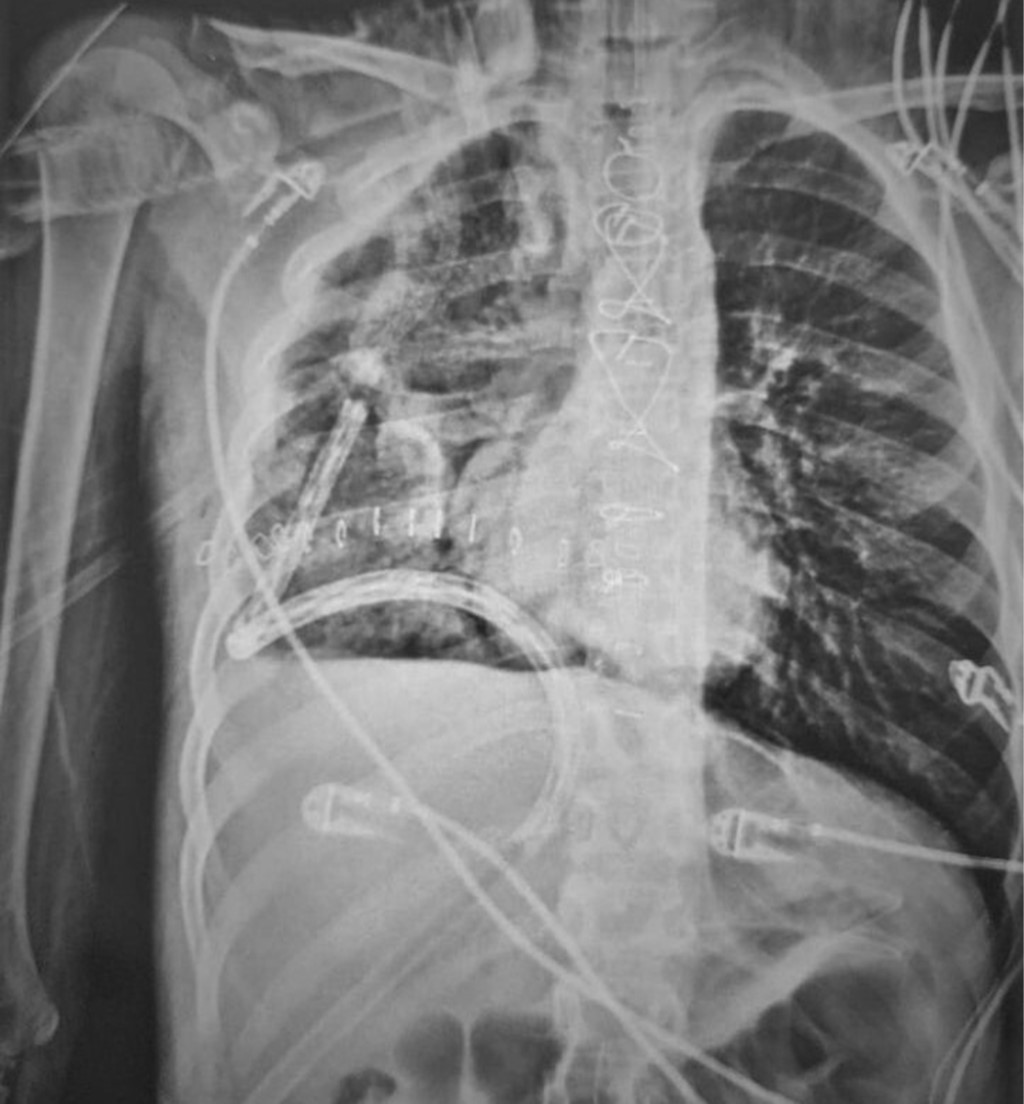

En la radiografía de tórax se observa hemitórax derecho una radiopacidad heterogénea que ocupa 60%, dos imágenes ovoideas en su ápice y ligero desplazamiento traqueal y mediastinal a la izquierda (Figura 1). La ecografía testicular fue normal.

Se inicia esquema de tratamiento basado en tres ciclos de quimioterapia neoadyuvante estándar con bleomicina, etopósido y cisplatino. Los marcadores tumorales después de la quimioterapia mejoraron notablemente durante los primeros dos ciclos; sin embargo, el control radiográfico mostró un crecimiento tumoral que ocupa 80% del hemitórax derecho con aumento en el desplazamiento de las estructuras mediastinales (Figura 2). Se optó por continuar el tercer ciclo de quimioterapia, los marcadores tumorales permanecieron sin cambios, se decide realizar tomografía toracoabdominal como estudio de extensión para descartar metástasis. Lamentablemente, se evidencia un crecimiento exponencial del tumor que ocupaba 100% del hemitórax derecho y mediastino anterior sobrepasando más allá de la línea media del cuerpo con colapso del pulmón derecho, desplazamiento del corazón y grandes vasos hacia el lado izquierdo así como los componentes del mediastino posterior como tráquea y esófago, el abdomen sin evidencia de metástasis (Figura 3). Se realizó ecocardiograma transtorácico con datos de disfunción diastólica del ventrículo derecho con compresión de la aurícula derecha y vena cava inferior, hipertensión arterial pulmonar moderada, levocardia, levoapex, desplazamiento extremo del corazón a la línea axilar media, lo que implicaba empeoramiento clínico de nuestro paciente.